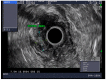

Gastric and esophageal tumors are diverse neoplasms that involve mucosal and submucosal tissue layers and include squamous cell carcinomas, adenocarcinomas, spindle cell neoplasms, neuroendocrine tumors, marginal B cell lymphomas, along with less common tumors. The worldwide burden of esophageal and gastric malignancies is significant, with esophageal and gastric cancer representing the ninth and fifth most common cancers, respectively. The approach to diagnosis and staging of these lesions is multimodal and includes a combination of gastrointestinal endoscopy, endoscopic ultrasound, and cross-sectional imaging. Likewise, therapy is multidisciplinary and combines therapeutic endoscopy, surgery, radiotherapy, and systemic chemotherapeutic tools. Future directions for diagnosis of esophageal and gastric malignancies are evolving rapidly and will involve advances in endoscopic and endosonographic techniques including tethered capsules, optical coherence tomography, along with targeted cytologic and serological analyses.